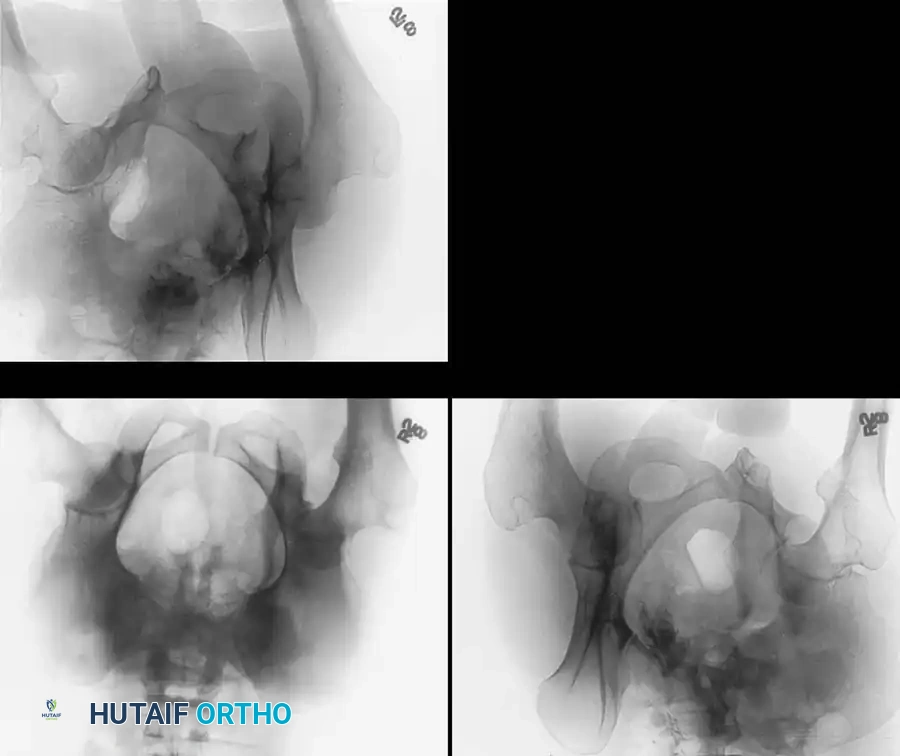

To fully conceptualize the fracture in three dimensions, the 45-degree oblique views described by Judet are mandatory:

* Iliac Oblique View: The patient is rolled 45 degrees toward the uninjured side. This view profiles the posterior column and the anterior wall of the acetabulum.

* Obturator Oblique View: The patient is rolled 45 degrees toward the injured side. This view profiles the anterior column and the posterior wall of the acetabulum.